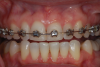

(9.) A thermoplastic tray made directly in the mouth over orthodontic braces facilitates caries control and places the 10% carbamide peroxide into the braces to chemically and mechanically clean them.

Figure 9

(10.) Removal of the tray demonstrates how well the bleaching material penetrates the brackets and arch wires.

Figure 10